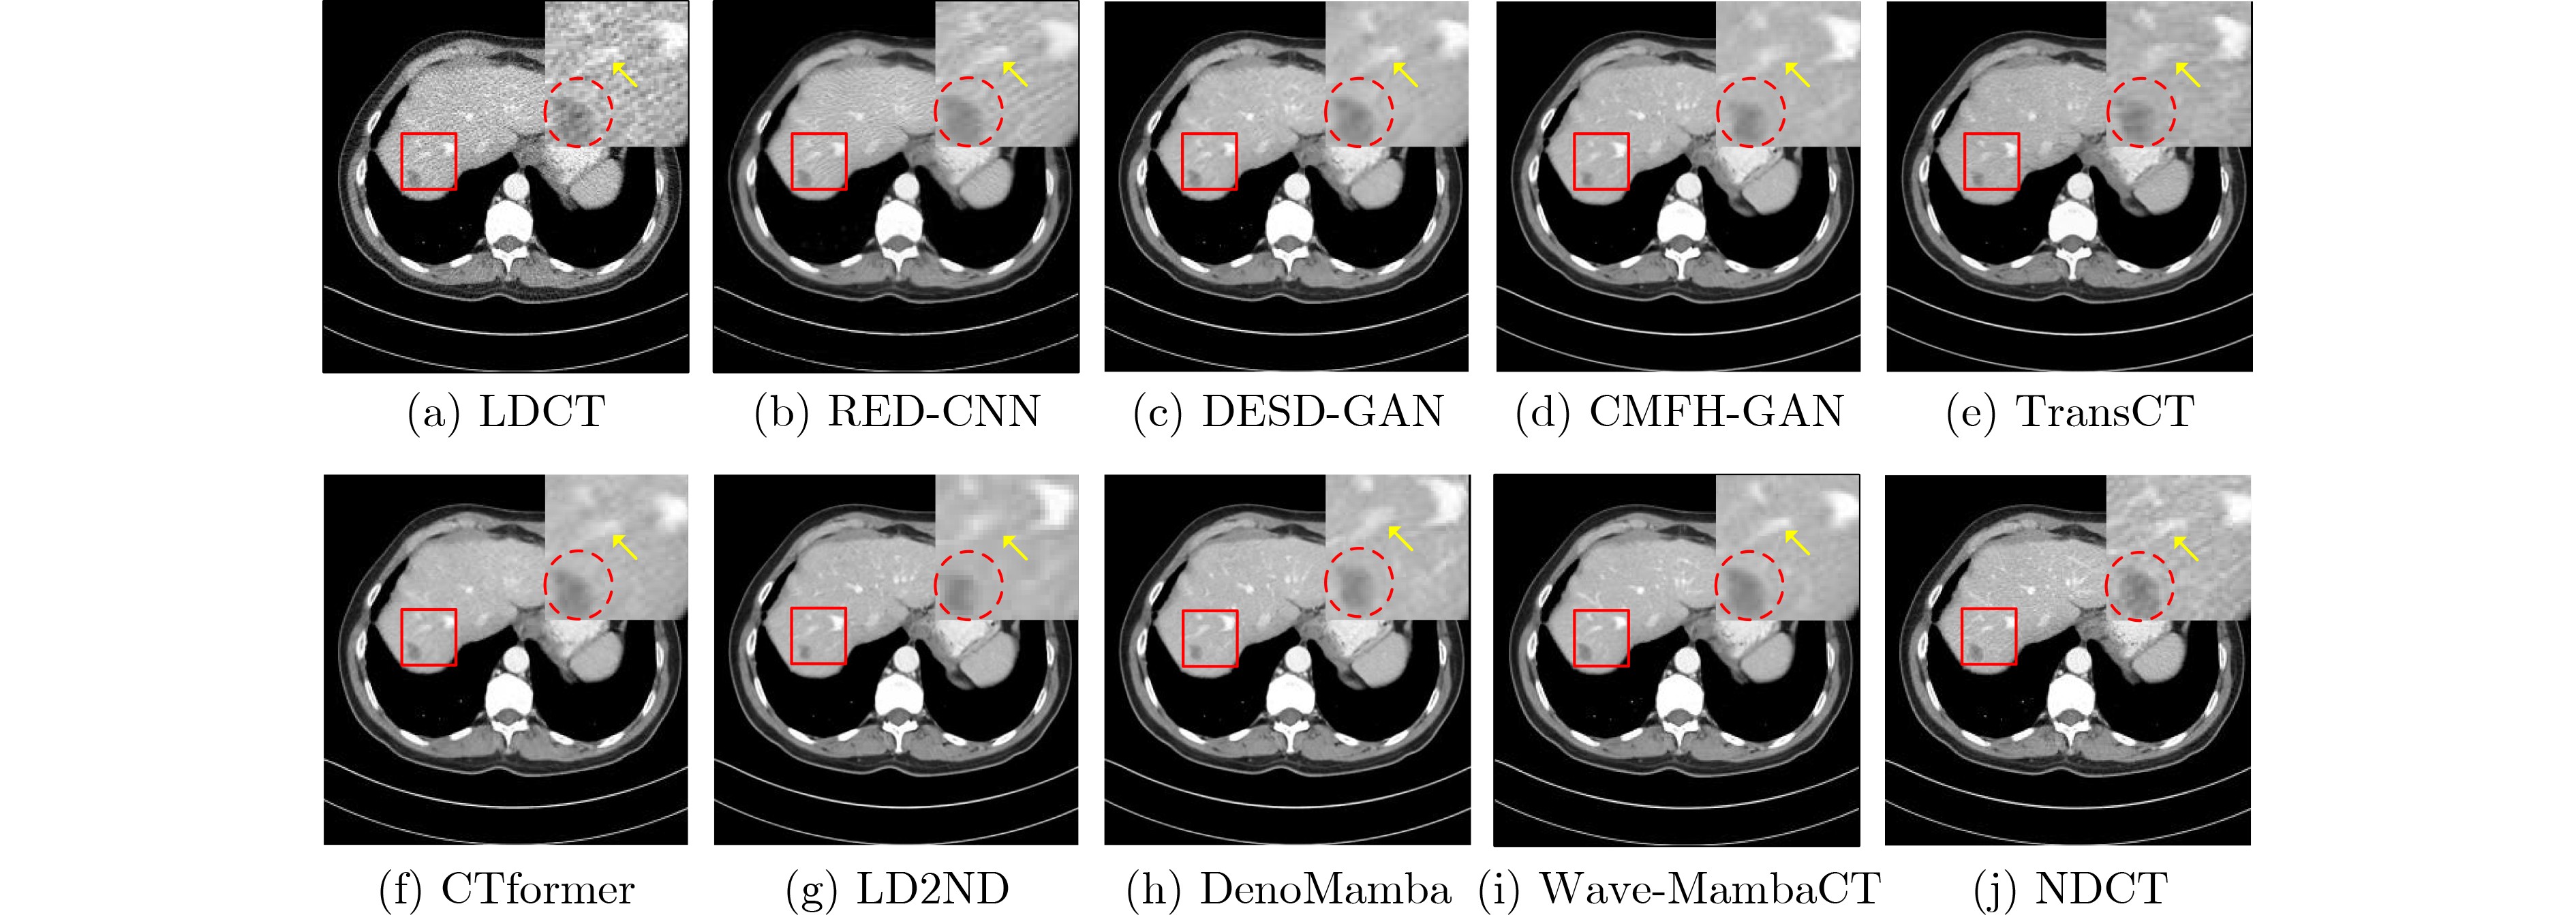

Wave-MambaCT:基于小波Mamba的低剂量CT伪影抑制方法

崔学英, 王宇航, 刘斌, 上官宏, 张雄

2026, 48(3): 982-993. doi: 10.11999/JEIT250489

摘要:

低剂量CT(LDCT)图像中的伪影和噪声影响疾病的早期诊断和治疗。基于卷积神经网络的去噪方法在远程建模方面能力有限。与Transformer架构的远程建模方法相比,基于Mamba模型在建模时计算复杂度低,然而现有的Mamba模型存在信息丢失或噪声残留的缺点。为此,该文提出一种基于小波Mamba的去噪模型Wave-MambaCT。首先利用小波变换的多尺度分解解耦噪声和低频内容信息。其次,构建残差模块结合状态空间模型的Mamba模块提取高低频带的局部和全局信息,并用无噪的低频特征通过基于注意力的跨频Mamba模块校正并增强同尺度的高频特征,在去除噪声的同时保持更多细节。最后,分阶段采用逆小波变换渐进恢复图像,并设置相应的损失函数提高网络的稳定性。实验结果表明Wave-MambaCT在较低的计算复杂度和参数量下,不仅提高了低剂量CT图像的视觉效果,而且在PSNR,SSIM,VIF和MSE 4种定量指标上均优于现有的去噪方法。